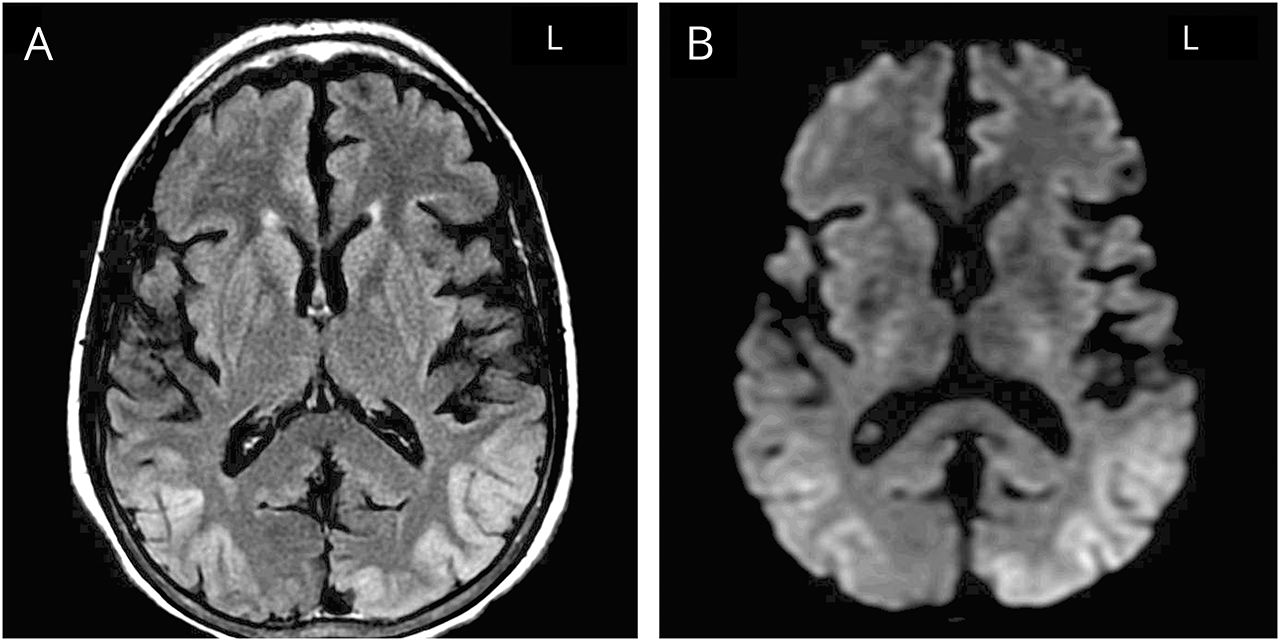

实验室检测显示钠125毫克当量/ L。CT扫描的头部没有对比显示没有异常。磁共振成像的大脑与对比表明两国parieto-occipital皮质T2 hyperintensities有限主要是大脑皮层灰质与扩散限制在相同的分布(图)。没有质量、梗塞或异常增强了。连续视频脑电图显示快速振荡对枕活动,然后将缓慢慢spike-and-wave与一些前传播模式。这往往是紧随其后的是快速左枕活动,spike-and-wave放缓。该模式符合电记录的癫痫持续状态。视频,病人在这个时期积极症状,断断续续的眼睛偏差和发作减少质疑,有时说话和支持视觉幻觉。抽搐发作、focal-motor表现或其他的情景性发作的事件从未目睹整个住院治疗。

图 核磁共振成像的大脑

(一)轴向t2加权fluid-attenuated反转恢复序列显示双边parieto-occipital皮质hyperintensities局限主要是大脑皮层灰质。(B) Diffusion-weighted成像序列显示轻微的扩散限制在相同的分布。

考试结果包括动眼神经的失用症、simultanagnosia和视神经共济失调没有全球生产总值(gdp)的变更与PSE的精神状态一般。MRI显示双边parieto-occipital皮质T2 hyperintensities,促使脑电图,揭示焦枕叶癫痫持续状态。综上所述,这些研究结果最符合Balint综合症引起的焦点nonconvulsive癫痫持续状态。

我们描述一个案件Balint综合征由于双边枕nonconvulsive癫痫持续状态。病人的复发PSE的历史和阿片类药物使用导致初始诊断混乱和由于她投诉的性质,眼科是呼吁神经综合症被发现之前的咨询。Balint综合征继发于nonconvulsive癫痫持续状态(NCSE)很少被报道在过去,和从未与PSE酒精性肝硬变的设置。1脑电图在这种情况下显示频繁交替左,右侧“乒乓球”枕叶癫痫和T2双边parieto-occipital hyperintensities和扩散限制MRI最有可能是由于这种不断发作的活动。